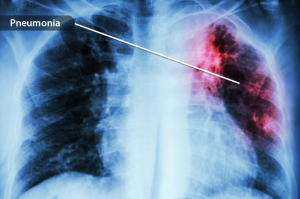

Seperti Apa Penampakan Pneumonia COVID, Kenali Gejala Dasarnya

Pneumonia COVID adalah kondisi kesehatan serius yang dapat merusak paru-paru. Ini adalah salah satu kasus parah serangan COVID yang bisa berakibat fatal. Pneumonia COVID berbeda